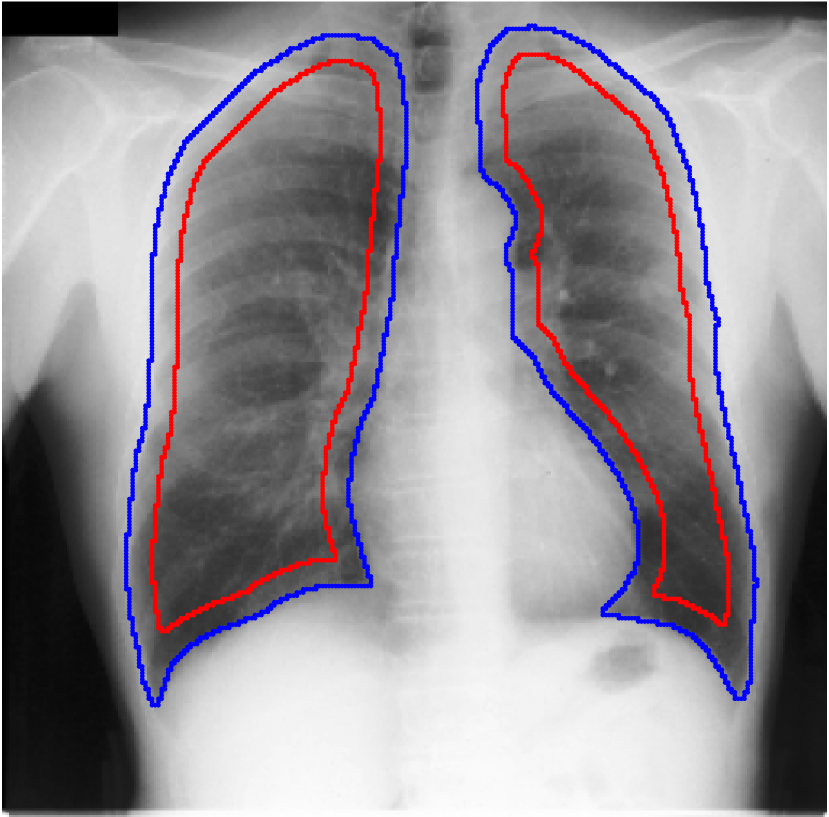

Table 1 shows the segmentation results of different methods with synthetic noisy label settings on JSRT , ISIC 2017 and Brats 2020 dataset. Note that QAM cannot be applied to Brats 2020 dataset because their network is designed for 2D only. We compare DICE score (DSC) on testing sets (against the clean labels). For each setting, we train 5 different models, and report the mean DSC and standard deviation. In and , where biases show up in noisy labels, the proposed method outperforms the baselines by a big leap in total case. The compared methods, however, only work when little bias is included, like . is equivalent to setting in our Markov model, resulting in . We also test the proposed method on real-world label noise, results shows in Table 2. Figure 5 shows examples of label correction results. We provide more qualitative results in the Appendix A.4.

Real-world label noise. To evaluate with real-world label noise is challenging. We are not aware of any public medical image segmentation dataset that has both true labels and noisy labels from human annotators. Therefore, we use a multi-annotator dataset, LIDC-IDRI dataset (Armato III et al., 2015; Armato et al., 2011; Clark et al., 2013), and the coarse segmentation in a vision dataset, Cityscapes (Cordts et al., 2016). The LIDC-IDRI dataset consists of 1018 3D thorax CT scans where four radiologists have annotated multiple lung nodules in each scan. The dataset was annotated by 12 radiologists, and it is not possible to match an annotation to an expert. We use the majority voting as the true labels and the union of four annotations as noisy labels. We process and split the data exactly the same way as Kohl et al. (2018). Cityscapes dataset contains 5000 finely annotated images along with a coarse segmentation by human annotators that we use as the “noisy label”. We only focus on the ‘car’ class because (1) cars are popular objects and are frequently included in images; (2) the coarse annotation of cars is very similar to noisy annotation in medical imaging – they are reasonable distortions of the clean label without changing the topology. See Figure 4(c) for an example. The detailed settings of LIDC-IDRI and Cityscapes can be found in Appendix A.2.1.